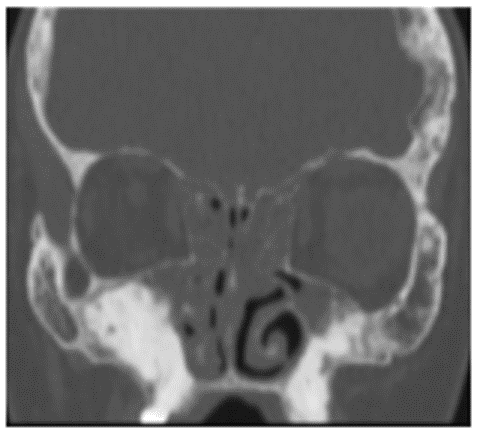

Остеома - КТ позволяет не только выявить наличие остеомы околоносовых пазух, но и определить тип ее строения, установить место исходного роста. Рентгеновская картина остеомы соответствует ее строению. Компактные остеомы - шаровидные, округлые опухоли, имеющие вид плотного, почти бесструктурного новообразования (рисунок 1).

Рис. 1. КТ околоносовых пазух, коронарная (А) и аксиальная (Б) плоскости: Компактная остеома решетчатого лабиринта справа в виде округлого добавочного интенсивного образования с четкими ровными контурами